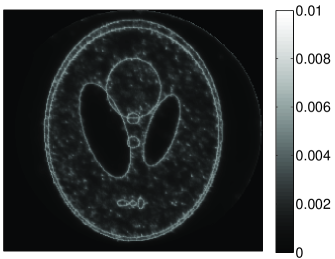

• [63] C. W. Dodge, A rapid method for the simulation of filtered X-ray spectra in diagnostic imaging systems (ProQuest, 2008).